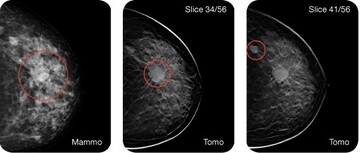

Η τομοσύνθεση (τρισδιάστατη μαστογραφία) είναι μια καινούργια σχετικά απεικονιστική εξέταση που δημιουργήθηκε με σκοπό να μειώσει τους περιορισμούς της ψηφιακής μαστογραφίας. Συνδυάζει τις κλασικές 2 λήψεις τις μαστογραφίας με μια δεύτερη κάμερα που λαμβάνει εικόνες σε γωνία 15 μοιρών, δημιουργώντας τελικά μια τρισδιάστατη εικόνα του μαστού. Το τελικό αποτέλεσμα είναι μια πλειάδα εικόνων (περίπου 50-60) πάχους ενός χιλιοστού, γεγονός που αυξάνει πολύ τη διακριτότητα της εξέτασης. Λειτουργεί ως επιπρόσθετο όπλο της μαστογραφίας, αν και ορισμένα κέντρα κυρίως του εξωτερικού τη χρησιμοποιούν και σαν μέθοδο screening όλων των γυναικών.

Από μελέτες φαίνεται πως αυξάνει τον αριθμό καρκίνων που ανιχνεύονται κατά 30% περίπου ενώ παράλληλα μειώνει τις μη απαραίτητες βιοψίες και περαιτέρω εξετάσεις κατά 30%. Μεγάλη η συμβολή της στον έλεγχο των πυκνών μαστών όπου και έχει ίσως απόλυτη ένδειξη.